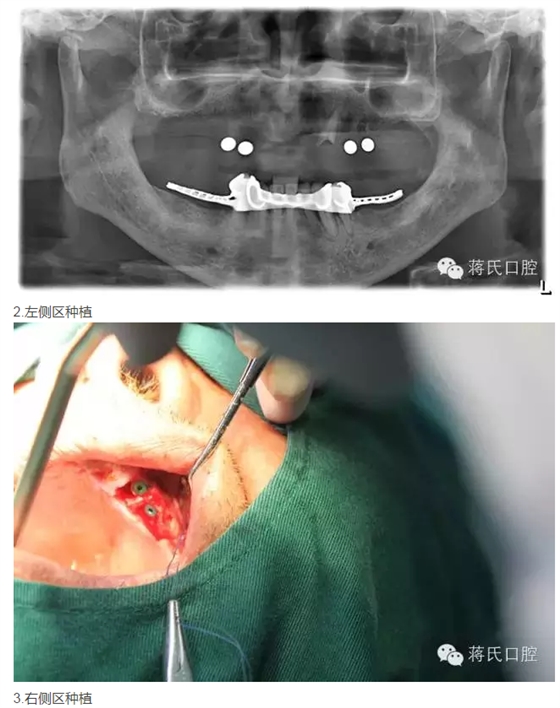

修復(fù)前全景片

2015年09月14日11:49 人氣:-

治療地點(diǎn) 大慶蔣氏口腔

種植醫(yī)師 蔣志剛

3兩側(cè)四五區(qū)種植共4顆

4活動(dòng)義齒雙重冠修復(fù)